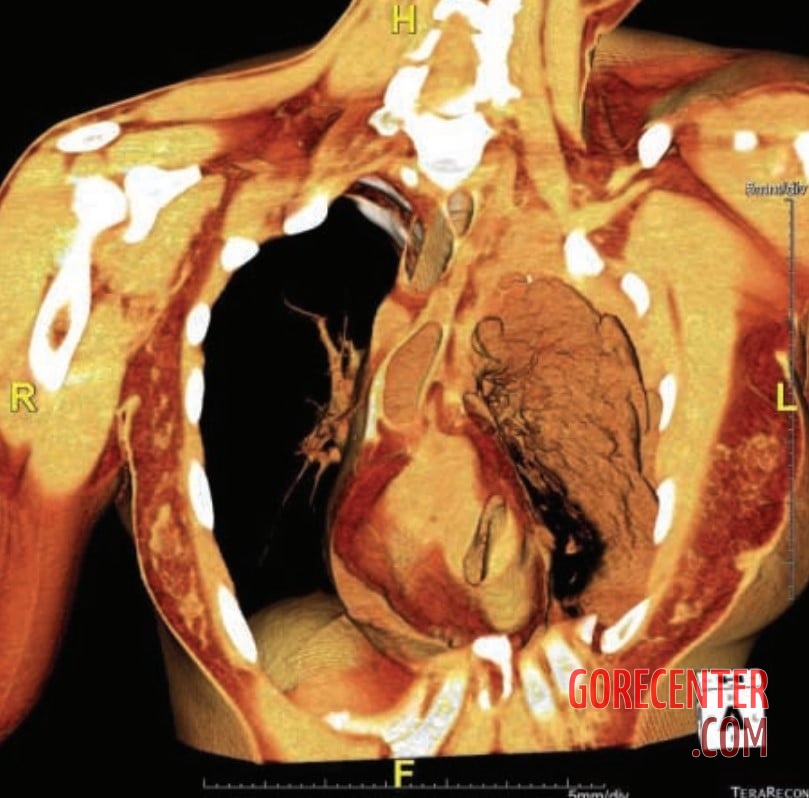

Photos taken during a forensic autopsy show a 41-year-old woman who died as a result of a stab wound to the heart. During an escalated argument, her husband grabbed a knife in a fit of rage and killed her with a single stab. The blade penetrated into the left ventricle, leading to a large accumulation of blood in the pleural cavity and the pericardium.